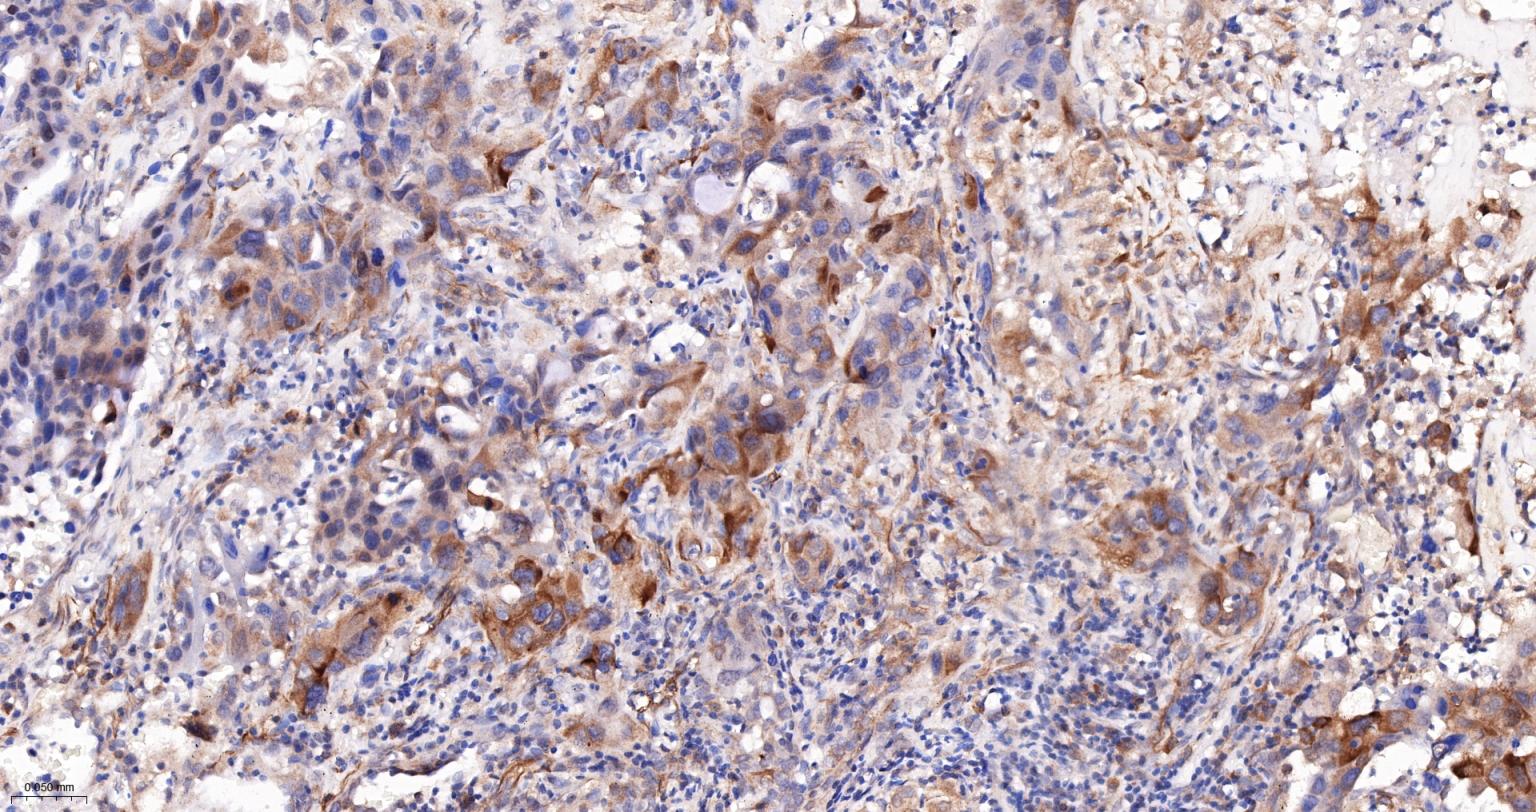

Paraformaldehyde-fixed, paraffin embedded Human Lung Cancer; Antigen retrieval by boiling in sodium citrate buffer (pH6.0) for 15 min; The section was incubated with phospho-RPS6 (Ser235+Ser236) Polyclonal Antibody, Unconjugated (bs-3388R) at 1:400 overnight at 4°C, followed by conjugation to the bs-0295G-HRP and DAB (C-0010) staining.